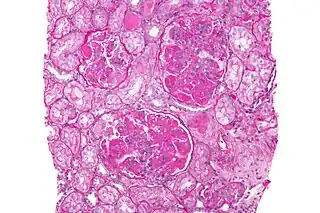

Manifestaciones renales

Se encuentra afectación renal clínica aproximadamente un 50 % de los pacientes; sin embargo, la mayoría del resto de pacientes tiene enfermedad subclínica que se puede observar si se realiza una biopsia renal. La afectación renal habitualmente ocurre en los primeros años de la enfermedad y debería ser detectada de modo temprano mediante análisis periódicos de orina y de la función renal.[59] Una hematuria o proteinuria indoloras suelen ser el único hallazgo inicial renal. La afectación renal es una de las principales causas de morbilidad y mortalidad en LES; aunque, debido al reconocimiento y tratamiento precoz, las últimas fases de enfermedad renal crónica se observan en menos del 5 % de los paciente. Pueden presentarse diversas formas de glomerulonefritis, siendo la biopsia renal necesaria para determinar el tipo y la extensión de la afectación renal.[59]

En 2004 se desarrolló un sistema de clasificación de la nefritis lúpica, denominado clasificación ISN (International Society of Nephrology) determinada por la biopsia renal.[60]

- Nefritis lúpica con cambios mínimos mesangiales (clase I).

- Nefritis lúpica con proliferación mesangial (clase II).

- Nefritis lúpica focal (clase III).

- Nefritis lúpica difusa (clase IV).

- Nefritis lúpica membranosa (clase V).

- Nefritis lúpica esclerosante evolucionada (clase VI).

Además de las lesiones glomerulares hay otras formas de enfermedad renal en el LES, incluyendo nefritis tubulointersticial, enfermedad vascular, microangiopatía trombótica y lupus podocitopatía.[61]